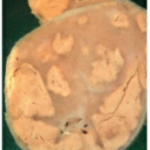

Specimens Tuberculous (Tb) Lymphadenitis

Specimens Tuberculous (Tb) Lymphadenitis 1. What is this specimen? Specimen of lymph nodes that are matted. The cut surface shows caseation. Hence, it is tuberculous lymphadenitis. "What is tuberculous lymphadenitis?" 2. What is the microscopic picture? Central caseation is surrounded by epithelioid cells, Langhans type of giant cells. 3. What are the … [Read more...] about Specimens Tuberculous (Tb) Lymphadenitis